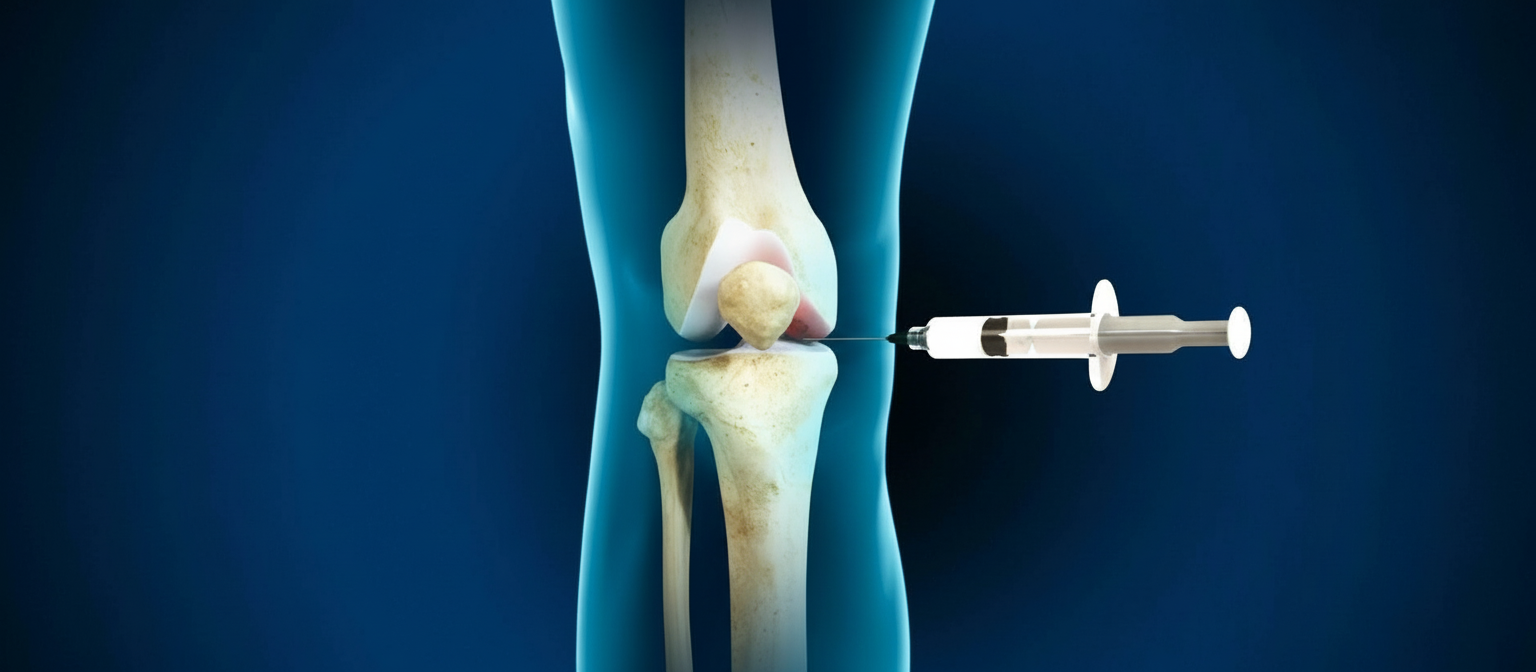

Infiltração articular com ácido hialurônico: orientações para pacientes

O que é a infiltração com ácido hialurônico? A infiltração articular com ácido hialurônico é um procedimento médico minimamente invasivo. Nele, o médico aplica o ácido hialurônico diretamente na articulação afetada. O ácido hialurônico está naturalmente presente no líquido sinovial, que ajuda a lubrificar as articulações. Por isso, a infiltração pode contribuir para: Além disso, o procedimento pode fazer … Ler mais